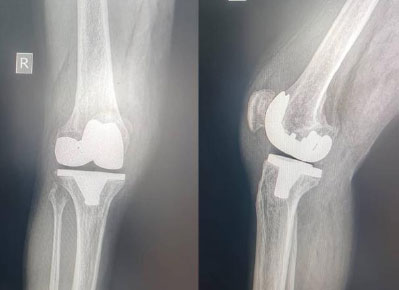

A femoral notch (anterior cortical cut) was observed in three cases, without notable clinical consequences. Two cases of prosthetic loosening were detected after two years postoperatively, occurring in one obese patient (Fig. 7a,b) and in one patient with rheumatoid arthritis.

(a) A 56-year-old obese female patient (BMI = 42): (b) radiograph of both knees showing early loosening of the tibial baseplate and marked polyethylene insert wear at two-year follow-up of a right total knee arthroplasty; severe left knee osteoarthritis, classified as Ahlbäck stage IV.